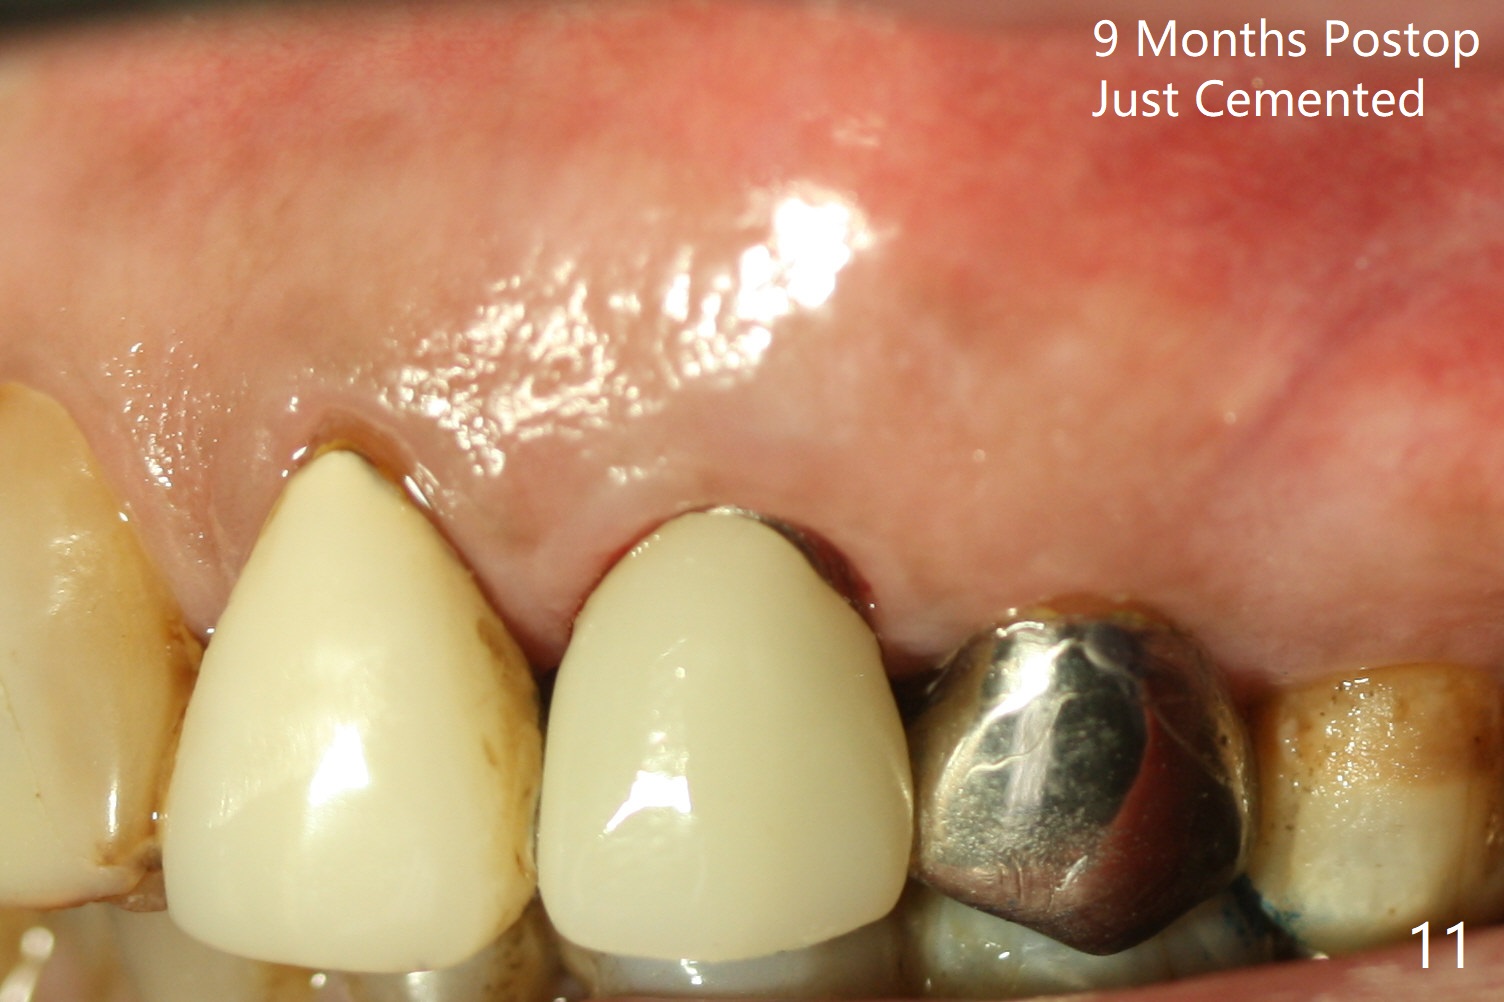

Extraction of the residual root at #11 (Fig.1) turns out to be difficult (Fig.2 (arrow: after use of small elevator). The tooth is sectioned (Fig.2 *); the palatal portion is removed, while the buccal one is trimmed until new moon-shaped and subgingival (Fig.3 * (gauze (G) packed in the socket while photo taking)). Initial osteotomy is 20 mm deep with nasal floor perforation (Fig.4). The subsequent depth is 17 mm (Fig.5). When a 5x17 mm tissue-level implant is placed (Fig.6,7; >60 Ncm), there is a gap between it and the socket shield (Fig.6 *). Gap-filling Vera Graft (Fig.8 *) also covers the shield prior to fabrication of an immediate provisional (Fig.9). There is no apparent bone loss 3.5 months postop (Fig.10). There is no buccal plate resorption 9 months postop (Fig.11). The implant is doing well 2 years postop (1 year 9 months post cementation, Fig.12).